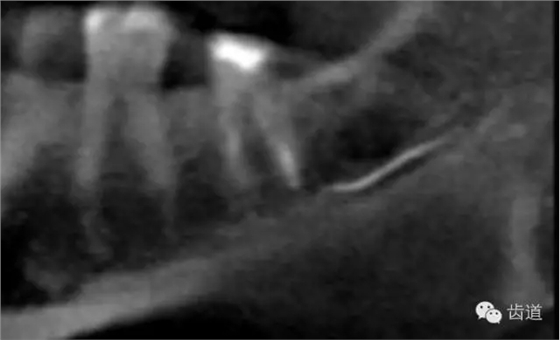

(3)髓室底穿孔:處理方法同上。同時(shí)找到根管口,按常規(guī)進(jìn)行根管預(yù)備和充填。如穿孔范圍太大易導(dǎo)致根分歧病變,予后欠佳??尚懈芡饪啤?/span> (4)根管壁形成臺(tái)階:先換小號(hào)銼去除臺(tái)階,再順序擴(kuò)挫。如根管壁穿孔,找到主根管進(jìn)行預(yù)備后,主根管及側(cè)穿道同時(shí)充填。在根尖1/3或根尖彎曲處側(cè)穿,根充后,配合根尖手術(shù)——根切+倒充填。 (三)髓腔壁穿孔的預(yù)防 1.掌握每個(gè)牙齒的髓腔解剖形態(tài)及其在牙齒表面的投影范圍。 2.術(shù)前拍X線片。 3.進(jìn)行規(guī)范化操作,隨時(shí)與X線片核對(duì)器械進(jìn)入方向及進(jìn)入深度。 器械折斷在根管內(nèi),阻塞根管,妨礙治療操作。如不能取出,使根管治療不能繼續(xù)進(jìn)行,不得不輔以根尖手術(shù)。 左上7近中頰根器械折斷 右上6腭根器械折斷 1.器械本身的原因 材料質(zhì)量欠佳,受力后易折斷。 器械反復(fù)使用,產(chǎn)生折痕,用力后也易折斷。 消毒方法不當(dāng),消毒液中未放防銹劑,器械銹蝕易折。 2.術(shù)者器械使用不當(dāng) 遇有阻力,仍強(qiáng)行進(jìn)入,用力過(guò)大過(guò)猛,超過(guò)了器械所能承受的程度 未按操作要求使用器械(跳號(hào)) 器械在細(xì)窄根管內(nèi)被卡住后,仍勉強(qiáng)旋轉(zhuǎn)器械柄 折斷于根管內(nèi)的器械要盡量取出,若無(wú)法取出經(jīng)常規(guī)充填后,成功率不受明顯影響。 1.折斷器械有一部分露在根管口外,用鑷子或持針器夾取出。 2.器械斷端在根管口內(nèi):用超聲根管銼在該器械旁增隙,通過(guò)超聲震蕩和沖洗,可將折斷器械從根管內(nèi)震動(dòng)沖出。在手術(shù)顯微鏡下直視操作,大大提高了取出的成功率。 3.折斷器械尖端已超出根尖孔:無(wú)癥狀不處理;有疼痛則作根尖手術(shù)取出。 4.折斷器械較長(zhǎng),各種方法均不能取出,可作根管電解消毒,塑化治療或塑化劑處理,根管充填。 若患牙根尖有病變,必要時(shí)作根尖切除+倒充填。 1.使用前認(rèn)真檢查器械有無(wú)生銹、折痕、螺紋松解等現(xiàn)象。 2.嚴(yán)格按器械使用規(guī)則進(jìn)行操作。 3.使用機(jī)用根管器械,應(yīng)支點(diǎn)穩(wěn)、轉(zhuǎn)速慢,并只能應(yīng)用于直的根管。 4.制備開(kāi)髓洞形時(shí),應(yīng)充分暴露根管口,對(duì)彎曲根管能盡量減少其彎曲度,對(duì)彎曲度在30o以上的根管盡量采用超聲根管預(yù)備并使用鎳鈦根管挫。 5.控制器械使用次數(shù):根管銼刃部的鋒利程度隨所預(yù)備的根管數(shù)目增加而降低。 25#以下器械只能用1—2次,30#—50#器械可用二次。 牙折分為冠折、根折及冠根折三種。根管治療后,由于牙折導(dǎo)致拔除者屢見(jiàn),故應(yīng)引起足夠重視。 (一)牙折發(fā)生原因 1.經(jīng)根管治療的牙齒,因失去了牙髓的營(yíng)養(yǎng)而脆性增大。 2.制備開(kāi)髓洞形時(shí),過(guò)多的磨除了牙體組織,削弱了牙體組織強(qiáng)度。 3.根管清理和成形以及做冠樁預(yù)備過(guò)程中,過(guò)多的磨除根管壁,削弱了牙根強(qiáng)度。 4.用牙膠做根管充填時(shí),側(cè)向或垂直壓力過(guò)大,均可造成牙根縱折。 5.其他:根管釘、樁的采用;熱塑冷凝的牙膠尖填入根管后自身體積膨脹;牙周受累的牙齒,支持骨喪失,也增加了牙折的機(jī)會(huì)。 (二)牙折的處理 應(yīng)盡可能保存患牙 1.冠折:根據(jù)折斷的牙體組織的多少及部位,可分別選擇充填;加螺旋釘固位;全冠或樁冠修復(fù)。 2.冠根折:折斷線在齦下不足3mm,配合齦切術(shù)或冠延長(zhǎng)術(shù),將斷端暴露在齦上,然后根據(jù)缺損情況考慮冠修復(fù)的種類。 折斷線在齦下超過(guò)3mm,患牙牙根較長(zhǎng),正畸力將牙根牽引,無(wú)條件做正畸治療的單根牙則拔除,多根牙則可做截根或半切除術(shù)。 3.根橫折:在冠方1/3處理方法同冠根折。 在根中1/3根折線不與牙周袋相通,做根內(nèi)固定,加牙冠部夾板固定4—8周。在根尖1/3,調(diào)合 解除創(chuàng)傷力,如有癥狀做根尖切除術(shù)。 4.根縱折:?jiǎn)胃绖t拔除;多根牙做截根術(shù)或半切除術(shù)。也有報(bào)告,用切開(kāi)翻瓣暴露縱折牙根,粘接劑粘合裂根的方法保留縱折牙牙根,若以后出現(xiàn)牙周袋則拔除。 (三)牙折的預(yù)防 1.根管治療過(guò)程中,有薄壁銳尖或陡峭的無(wú)基釉質(zhì),應(yīng)及時(shí)降低咬合或磨除。根管治療后,常規(guī)調(diào)合。 2.根管治療應(yīng)遵循:在保證治療的前提下,盡量保留健康的牙體組織。 3.根管充填操作用力適度。 五、下唇麻木 (一)發(fā)生原因:主要由下齒槽神經(jīng)損傷所致 1.治療操作中藥物、器械或根充物超出根尖孔,進(jìn)入下頜管損傷下齒槽神經(jīng) 2.解剖因素:下頜牙齒根尖距下頜管太近,有些牙根與下頜管相連,以下頜第二恒磨牙多見(jiàn) 左下7根充后下唇麻木 左下5根管預(yù)備后下唇麻木 (二)處理: 1.根據(jù)病史認(rèn)真查找原因,如為炎癥刺激所致,應(yīng)積極治療根尖周炎,加口服營(yíng)養(yǎng)神經(jīng)藥物。 2.理化刺激所致,口服營(yíng)養(yǎng)神經(jīng)藥物。 (三)預(yù)防: 1.作根管治療前拍X線片,下頜牙齒應(yīng)特別注意與下頜管的關(guān)系。 2.準(zhǔn)確測(cè)量根管工作長(zhǎng)度,各種操作均在工作長(zhǎng)度范圍內(nèi)進(jìn)行。根管封藥不可過(guò)飽和,防止藥液溢出根尖孔。 此種意外發(fā)生,給患者帶來(lái)很大的精神壓力,如器械落入呼吸道,則增加更大的痛苦,應(yīng)慎重處理。 (一)發(fā)生原因 1.術(shù)者精神不集中 2.患者過(guò)于緊張不合作 3.患者體位不正確 4.器械從手中滑脫 (二)處理 1.醫(yī)護(hù)人員應(yīng)鎮(zhèn)靜,安撫患者。 2.立即拍腹部平片。 3.落入消化道應(yīng)住院觀察。 4.服用長(zhǎng)纖維及有潤(rùn)滑作用的食物,勿服瀉藥。 5.適當(dāng)走動(dòng),勿劇烈運(yùn)動(dòng)。 6.每天拍腹部X線片,檢查大便至排出。 7.落入呼吸道,應(yīng)請(qǐng)耳鼻喉科或胸外科醫(yī)生協(xié)助取出。 (三)預(yù)防: 1.針對(duì)原因預(yù)防。 2.治療時(shí)上橡皮障。 3.無(wú)條件用橡皮障,可在器械柄拴安全鏈。 皮下氣腫是根管治療中少見(jiàn)的并發(fā)癥 (一)臨床表現(xiàn) 根據(jù)患牙的部位不同,可分別出現(xiàn)在頰部、頸部、和眶周等疏松軟組織迅速腫脹、充血,有捻發(fā)音。捻發(fā)音是組織氣腫的病理特征,以此和其他腫脹做鑒別。如空氣向頸部移動(dòng)可引起呼吸困難。 (二)發(fā)生原因 1.用壓縮空氣吹干根管時(shí)間過(guò)長(zhǎng)。 2.使用過(guò)氧化氫液沖洗根管,將藥液壓出根尖孔。 不可加壓??! (三)處理 一般不需特殊治療,給予抗生素預(yù)防感染 上頜竇曲霉病、上頜竇疼痛、上頜竇炎癥等。 根管治療的各種并發(fā)癥,絕大多數(shù)情況是由術(shù)者操作不規(guī)范所致。在根管治療過(guò)程中,術(shù)者應(yīng)嚴(yán)格按照規(guī)程進(jìn)行每一步操作,這些并發(fā)癥是完全可以避免的。